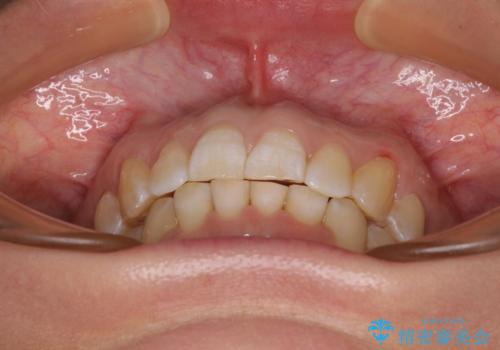

カリエールディスタライザーや部分的なワイヤー矯正を併用したことで、確実かつ短期間で治療を終えることができました。